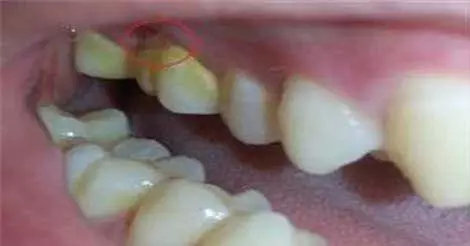

虽然每天都刷两次牙,但是外面的是干净了,但是里面却结了一层很硬的、黄黄的东西!这究竟是什么?

其实,这种黄色物质就是牙结石的初始形态,又被叫做牙垢,是沉积在牙面上已钙化的或正在钙化的菌斑及其他沉积物,一般是食物残渣、坏死脱落的口腔上皮细胞及唾液中的矿物质。

钙化是沿着牙菌斑附着牙面的内侧发生、持续进行的,刚开始形成时较软,大约数月后达到极点,就会如水壶里的水垢一样坚硬。虽然咀嚼食物、舌颊压力等原因,牙结石不会无限制地沉积,但牙结石终究不是什么好看的东西!

牙结石的规模壮大之后,就会开始扰袭你的牙齿,会慢慢侵蚀牙齿,特别是牙龈,这个时候刷牙刷出血、牙龈红肿、口臭什么的,统统都来了!